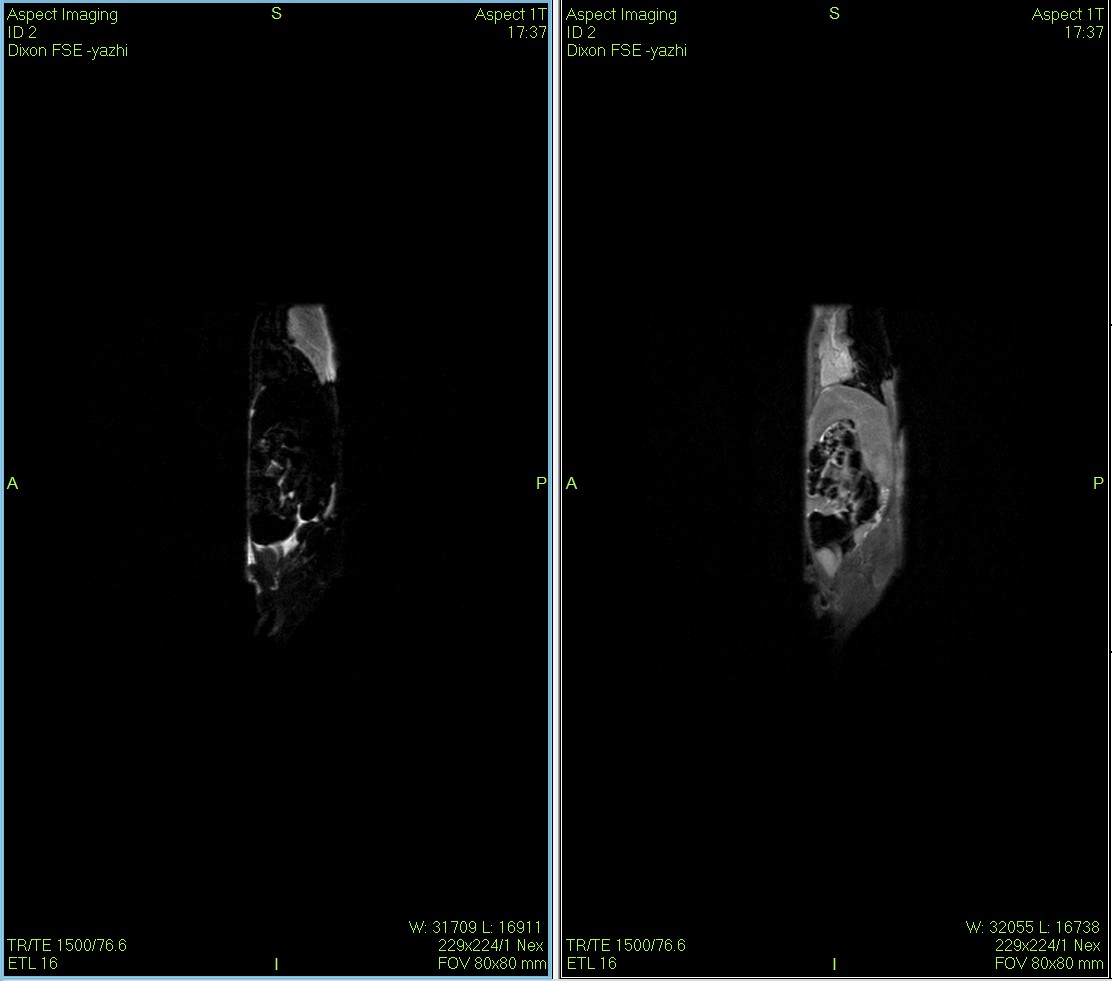

传统的体成分分析只能告诉我们“脂肪多了多少克”,而QMR的成像技术能告诉我们“脂肪长在了哪里”。本案例通过高分辨率的核磁成像,直观展示了高脂饮食小鼠腹部内脏脂肪 (Visceral Fat) 的显著堆积,实现了从“定量分析”到“形态学定位”的维度跨越。

低场核磁共振技术,已被广泛应用于小动物(大、小鼠)实验模型中,用于监测体内脂肪分布及沉积情况。这不仅有助于揭示人类肥胖代谢性疾病的病因,还为肥胖治疗药物的评价提供了重要依据。通过低场核磁共振技术结果表征,科研工作者能够直观地观察到小鼠体内脂肪的变化,从而更深入地理解肥胖症的发病机制。

Dixon脂肪抑制技术是由Dixon 提出,其基本原理是利用水、脂肪的化学位移差异,使用不同的回波时问,分别采集水和脂肪质子的in Phase 和 opposed -phase两种回波信号。

使用仪器: 小动物核磁共振成像仪NM21-040H-I 小动物核磁共振成像仪NM20-060H-I 小动物核磁共振成像仪NM42-040H-I